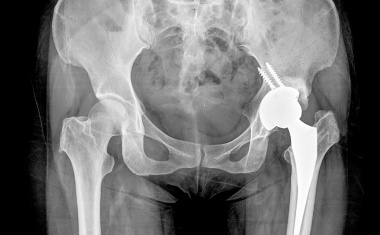

Ziel der Implantation eines künstlichen Hüft- und Kniegelenks ist die dauerhafte und stabile Verankerung der Prothese im Knochen. Nur so ist eine schmerzfreie Belastung des Kunstgelenks über idealerweise mehr als 20 Jahre möglich.